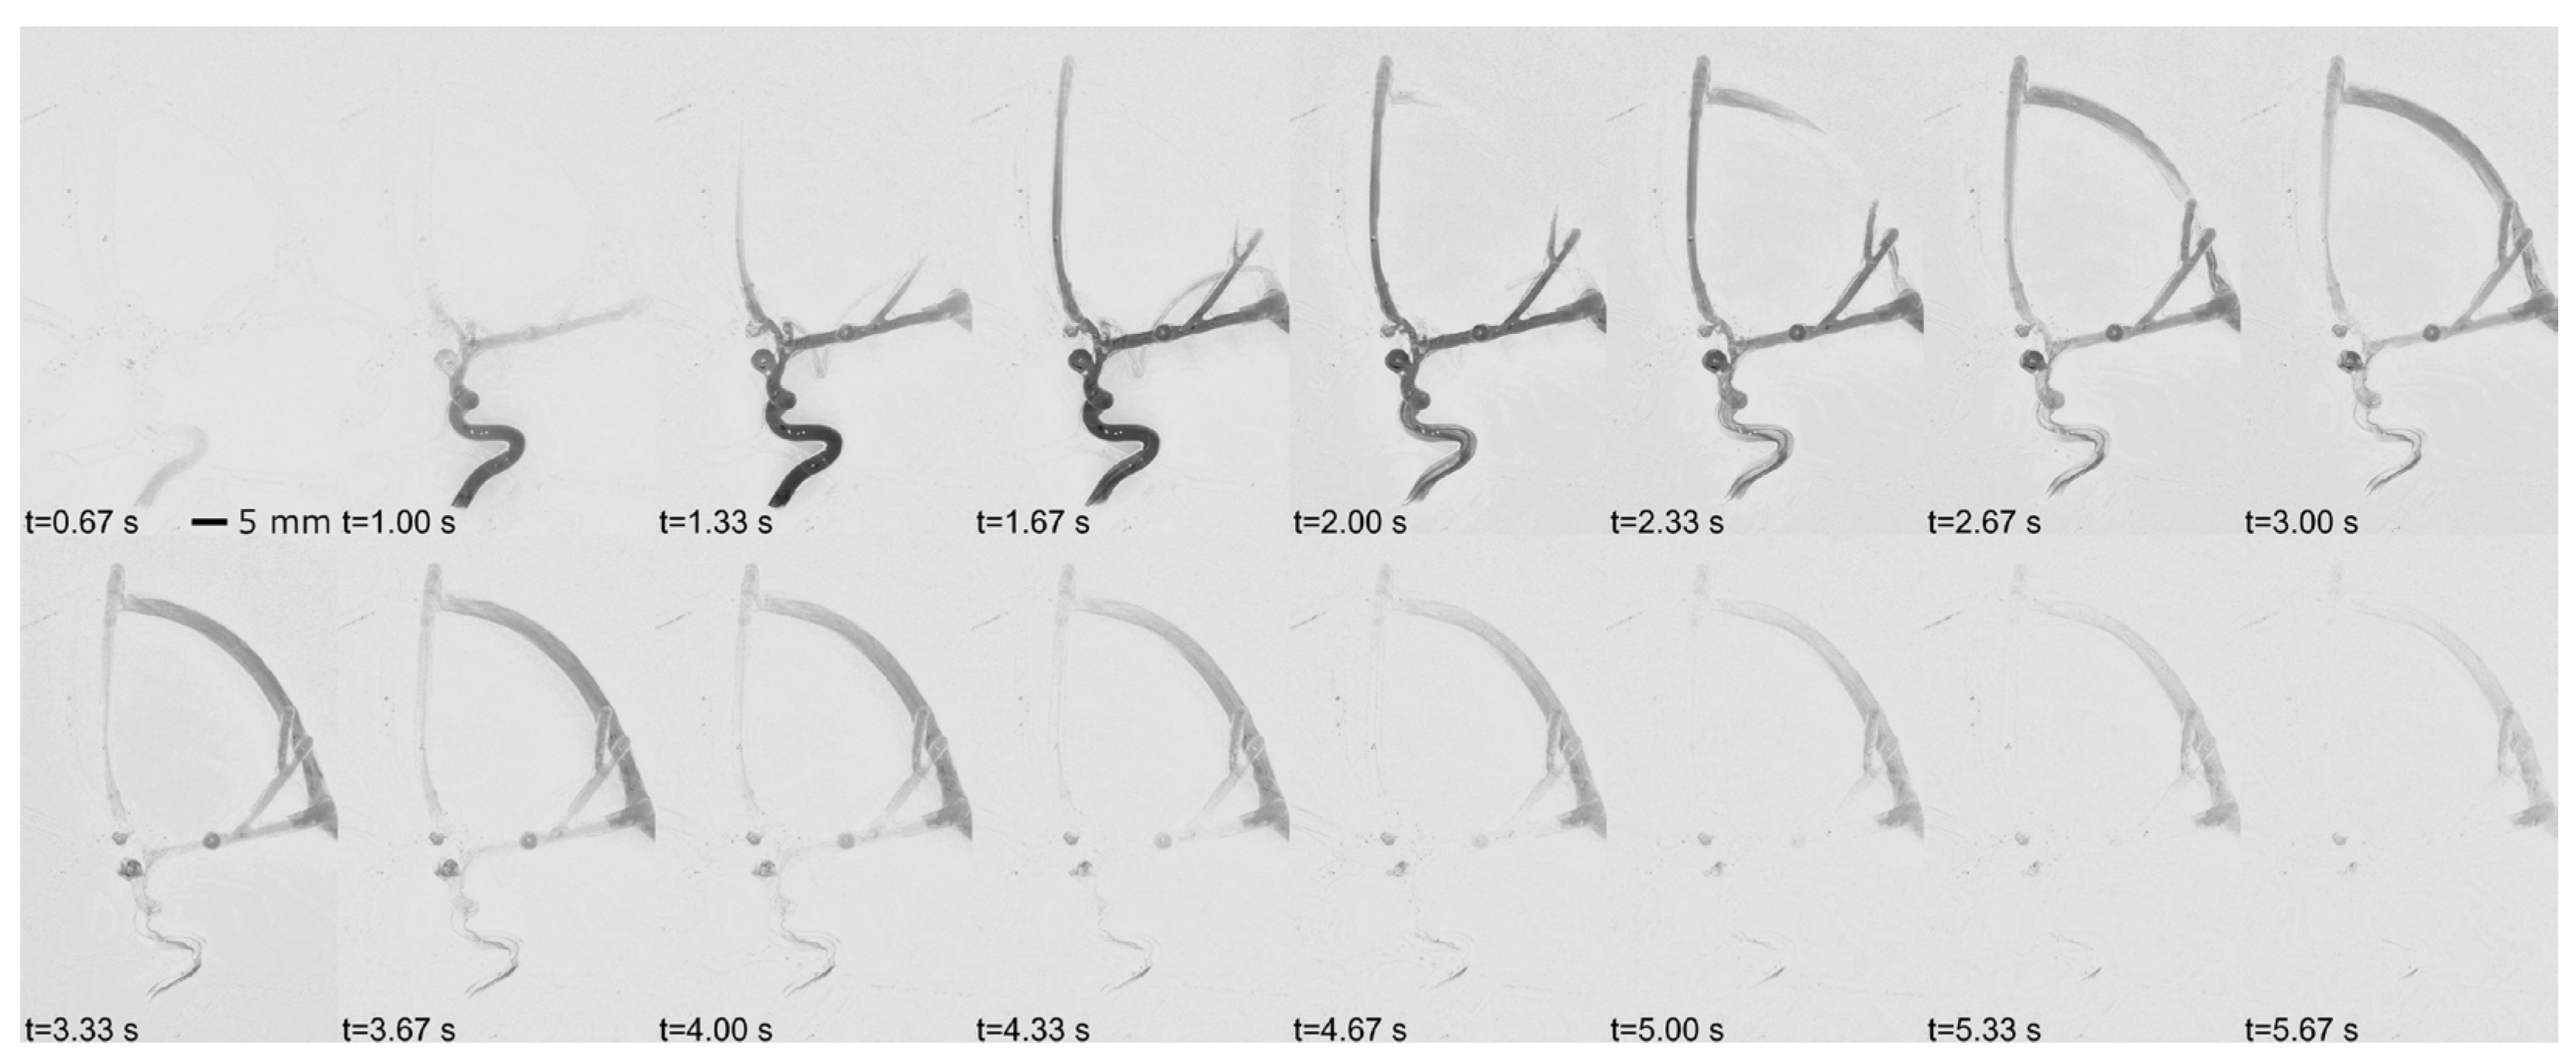

The DSA mode removes background structures to visualize contrasted vessels and fluid flow. First, the mask of the vascular structures without contrast agent is acquired when the “Cine” pedal is pressed. The program calculates the absolute difference between the grayscale live feed and the mask, highlighting changes where contrast agent is present. This image is then inverted to simulate real angiographic images, where vessels appear lighter. To further resemble original DSA images, a black background is blended with the inverted difference image, followed by additional image processing, such as brightness and adjustments, to refine the DSA. As shown in Figure 4, the images are processed and displayed at a reduced frame rate of 3 frames per second (fps), replicating the low fps used in actual DSA. All DSA images are stored and can be viewed as a loop forward and backward with the DSA Viewer, using designated keys on the numeric keypad.

Figure 4. Digital subtraction angiography (DSA) simulation. The visualization of contrasted vessels over time during a simulated DSA using AngioSim. The images show the progression of contrast agent flow through the vascular structures, captured at intervals of 0.33 s, from t = 0.67 s to t = 5.67 s. At t = 0.67 s, the first appearance of the contrast agent is visible.